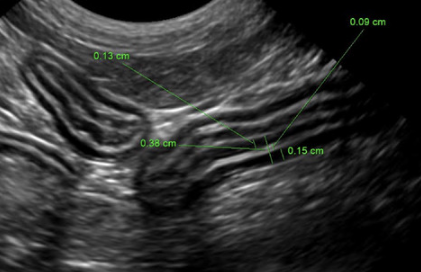

장벽 전체가 아닌 장벽의 근육층 비후를 가지고 추정한다는 논문이며

일단 정상 범위는

이것을 참고하자.